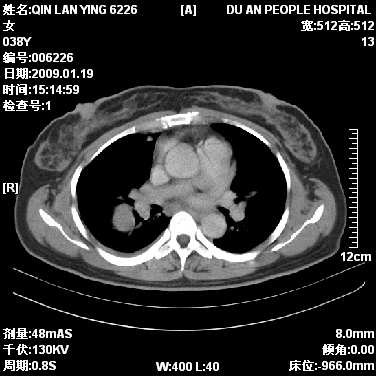

女,38岁,胸疼1个月。wbc:1万4

1)右肺中央型肺癌并右肺上叶阻塞性肺炎、节段性肺不张,纵隔淋巴结转移、右侧胸膜转移、肝脏转移。2)右侧胸腔少量积液。

1、右侧中央型肺癌并阻塞性肺不张,纵隔内、主动脉弓旁、右肺门淋巴结及肝脏转移可能性大,建议纤支镜进一步检查。

2、右侧胸腔积液。

本病例有几个容易诊断的地方:1、右肺上叶前段支气管闭塞,肺不张。2、淋巴结明显肿大。3、肝脏多个类圆形低密度影呈“牛眼征”改变,高度提示转移。